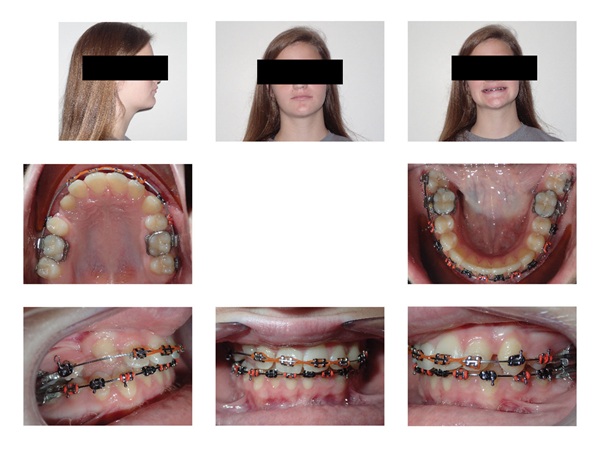

A 15-year-old female presented as a transfer patient after four years of active treatment elsewhere. Pre-treatment records taken when she was nearly 12 showed a case that appeared manageable—near-Class I occlusion, adequate maxillary arch space, and an ectopically positioned upper right canine that did not seem unusually difficult to address (Figs. 1–3). What arrived at the new practice was something considerably more complex.

Updated records told a different story. The upper right canine remained fully unerupted, and significant adverse canting of both arches had developed on the right side (Figs. 4–6). Root shortening was visible on the upper right canine, lateral, and central incisors, likely a consequence of prior reluxation attempts to encourage eruption. The upper incisors had also become markedly more proclined over the course of treatment, a known risk when ectopic canines prove resistant to traction. Comparing the pre-treatment and current lateral cephalometric radiographs illustrated just how much incisor angulation had shifted (Figs. 2, 10). Facial photographs suggested some lower-third asymmetry with a right-side deviation, though the lower arch canting appeared to have partially self-corrected after vertical elastics were discontinued (Figs. 7–8).

Fig. 7

Fig. 8